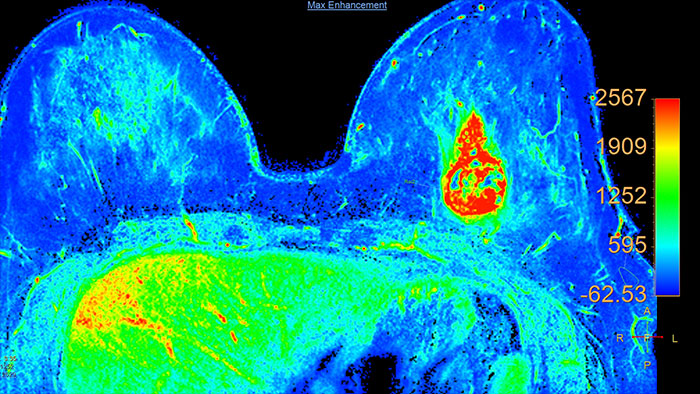

Support in assessing lesions by reviewing blood supply characteristics

Designed to evaluate time intensity curves of a T1 signal enhancement series. The application produces measurements including relative enhancement, maximum enhancement, time to peak (TTP), and wash-in/wash-out rates.